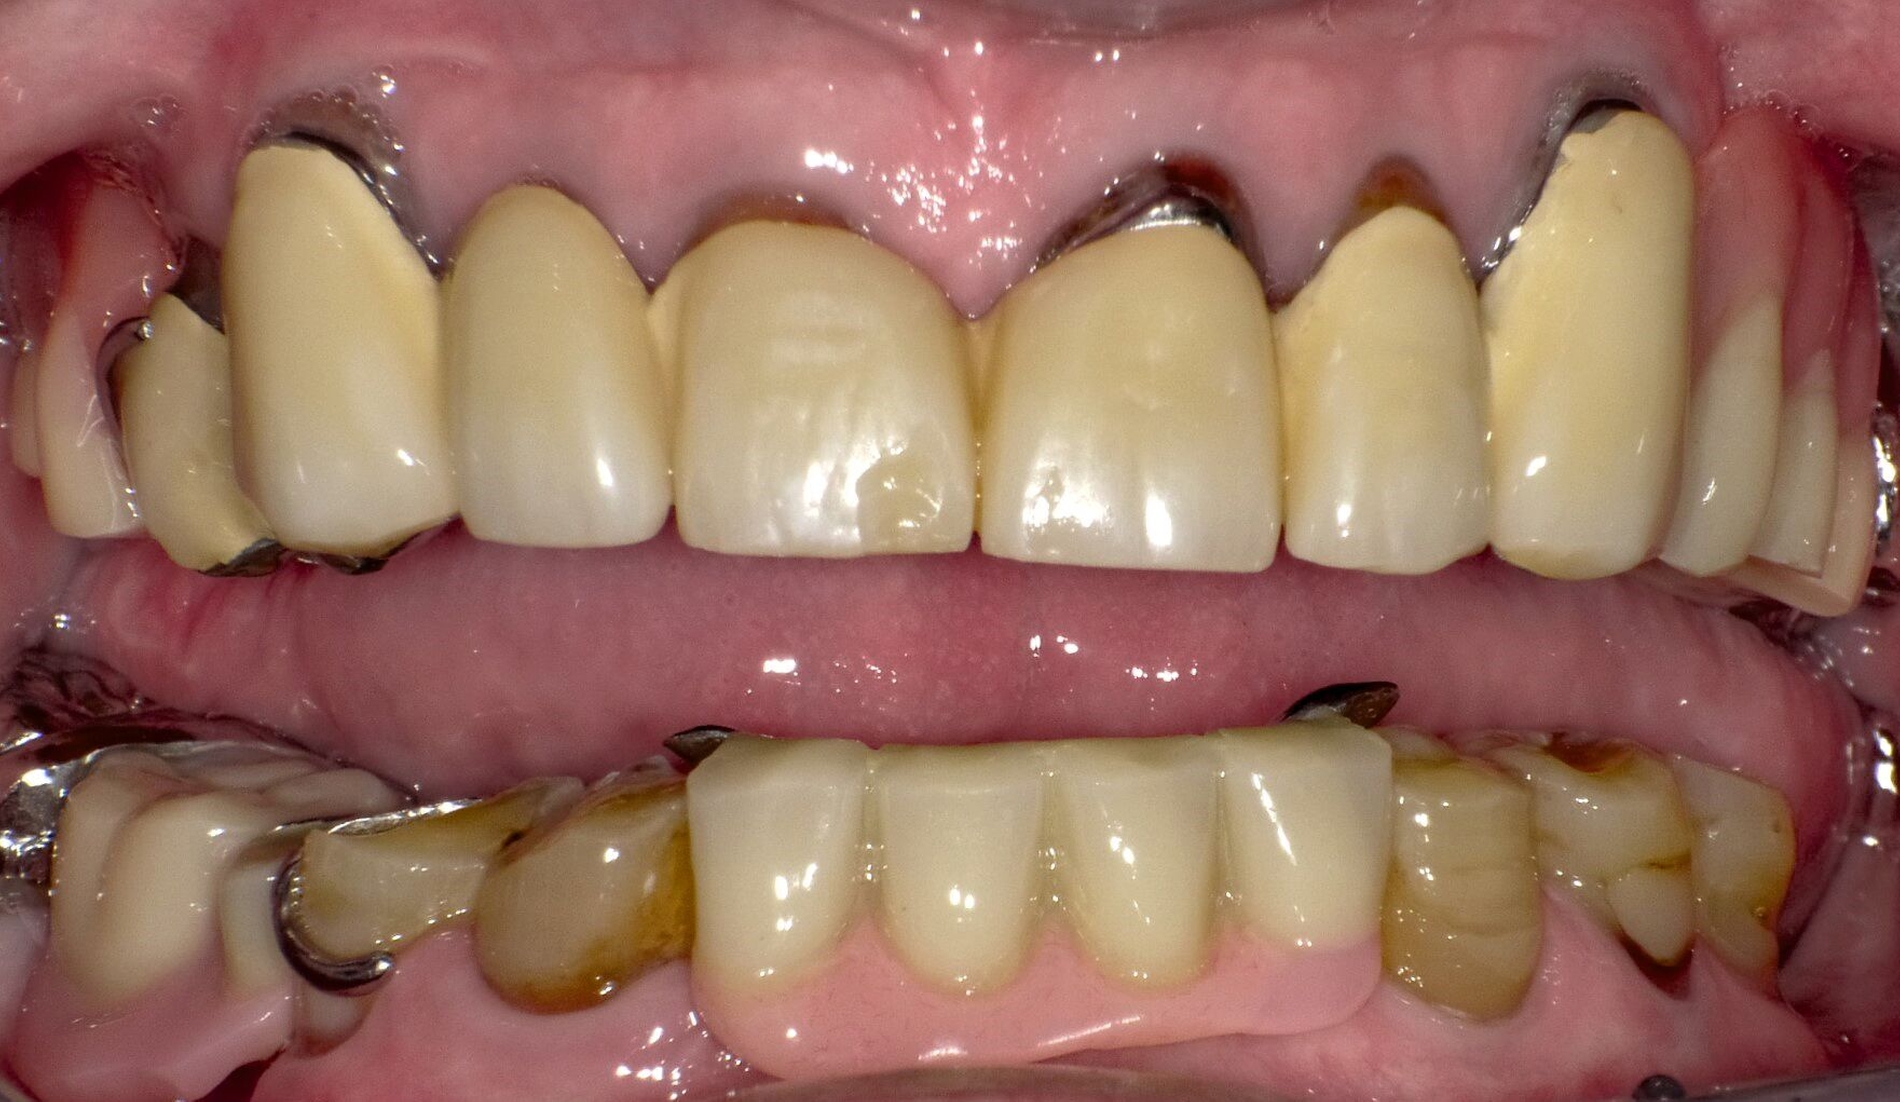

Nach siebenjähriger Tragezeit reduzierte sich der Allgemeinzustand der Patienten bedingt durch einen zweifachen Apoplex erheblich. Die Angehörigen bemühten sich bei nun fehlender Eigenverantwortlichkeit der Patientin um eine dauerhafte Aufnahme in eine Pflegeeinrichtung. Eine Vorstellung zur zahnärztlichen Kontrolle erfolgte nicht und die Patientin konnte unter ihrer ursprünglichen Adresse nicht mehr erreicht werden. Nach eineinhalbjähriger Abwesenheit wurde die Patientin mit Unterstützung ihrer Angehörigen wegen reduzierter Nahrungsaufnahme aufgrund von Schmerzen zur zahnärztlichen Behandlung vorstellig (Abbildung 3). Bei stark reduzierter Therapie- und Mundhygienefähigkeit wurde zusammen mit den Angehörigen entschieden, mehrere stark kariös und parodontal geschädigte Zähne zu entfernen und den vorhandenen Zahnersatz umzuarbeiten. Es lag nun eine BS 3 bis 4 vor.